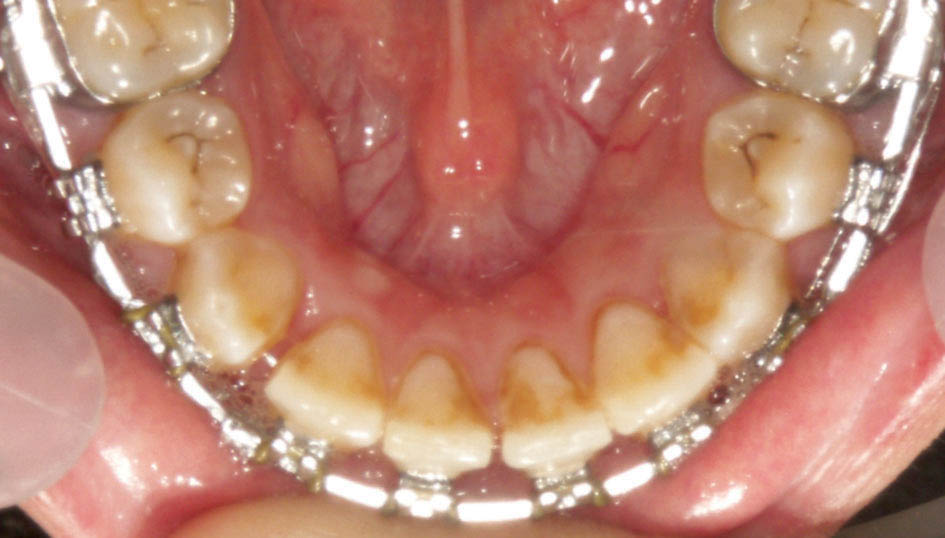

پس از برطرف شدن کرادینگ انسیزورها اگر باز هم Laceback محکم شود باعث جدا شدن کانین از لترال میگردد، لذا در این زمان Laceback را دیگر محکم نمیکنیم و باید سیم را ضخیم کنیم مگر در دو مورد: لترالهای کوچک یا Peg Shape برای اصلاح سایز دندان (شکل 16-3) و لترال پالاتالی که به همراه Off بودن میدلاین است (شکل 17-3).

شکل 16-3: لترالها با سایز کوچک

شکل 17-3: off بودن میدلاین به خاطر کرادینگ نا متقارن (لترال پالاتالی)